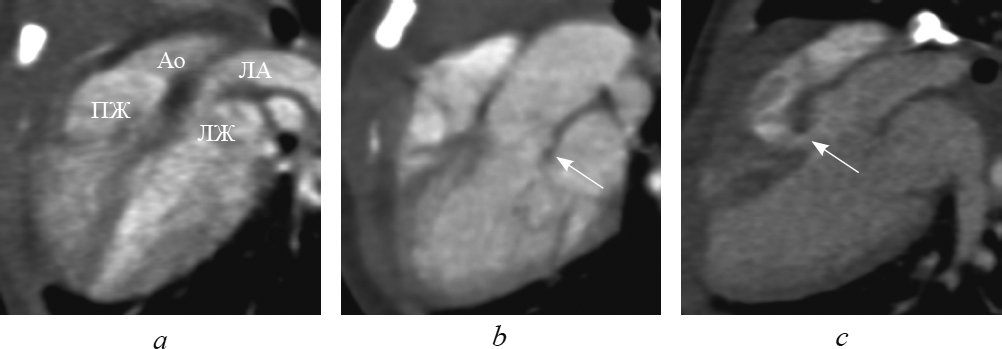

This article contents the results of computed tomography with intravenous bolus contrast media administration data analysis in children with transposition and congenitally corrected transposition of the great arteries with the consequental performing of the multiplanar heart-axis-oriented reformations. Among 148 examined children transposition of great arteries was detected in 13 patients (9 boys and 4 girls aged 1-144 day of life); congenitally corrected transposition was found in 4 cases of children aged from 6 months to 15 years and 6 months (2 boys and 2 girls). In this article comprehensive anatomical criteria of each heart chamber morphology are presented and reformations where these criteria can be seen are shown. Also in the article is given comparative characterization of heart and great arteries structures in transposition and congenitally corrected transposition in every certain heart-axis-oriented reformation. By the results of consequently performed heart-axis-oriented reformations data analysis the peculiar anatomical signs of transposition and congenitally corrected transposition are determined. The results of data analysis show that from the list of offered reformations the peculiar anatomical signs of both kinds of transposition are significantly determined in long-axis of right ventricle inflow tract reformation, left heart chambers reformation, supply ventricle division reformation, short-axis reformation at the level of great arteries. Computed tomographic angiocardiography heart-axis-oriented multiplanar reformations permit full and correct assessment of heart and main vessels, which is important for planning of surgical treatment in congenital heart diseases.